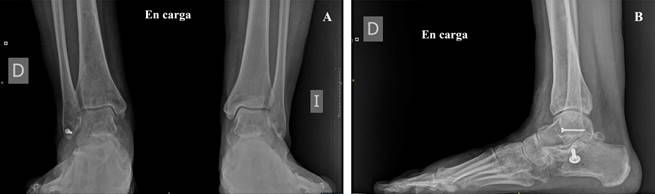

A las ocho semanas se retiró el fijador externo y se autorizó la carga progresiva y la movilización activa del pie y tobillo, con buena tolerancia. A los cinco meses la paciente ya había recuperado la sensibilidad en el arco plantar y el borde medial del primer dedo y únicamente persistía la hipoestesia en la almohadilla plantar en los territorios de inervación de los nervios plantar lateral y medial. A los seis meses de la lesión, la movilidad era completa (Figura 10) y únicamente presentaba cierta tumefacción y dolor retromaleolar. Las radiografías en carga mostraron una adecuada congruencia tibioastragalina y subastragalina (Figura 11) y la puntuación según la escala American Orthopaedic Foot and Ankle Society (AOFAS®) fue de 70 a los ocho meses, resultado que se considera muy satisfactorio dada la severidad de las lesiones iniciales.